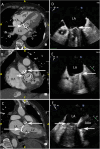

Infective Endocarditis (IE) remains a significant health challenge. Despite an increasing awareness, mortality is high and has remained largely unchanged over recent decades. Early diagnosis of IE is imperative and to assist clinicians several diagnostic criteria have been proposed. The best known are the Duke criteria. Originally published in 1994, these criteria have undergone significant modifications. This manuscript provides a timeline of the successive changes that have been made over the last 30 years. Changes which to a large degree have reflected both the evolving epidemiology of IE and the proliferation and increasing availability of advanced multi-modality imaging. Importantly, many of these changes now form part of societal guidelines for the diagnosis of IE. To provide validation for the incorporation of cardiac computed tomography (CT) in current guidelines, the manuscript demonstrates a spectrum of pictorial case studies that re-enforce the utility and growing importance of early cardiac CT in the diagnosis and treatment of suspected IE.